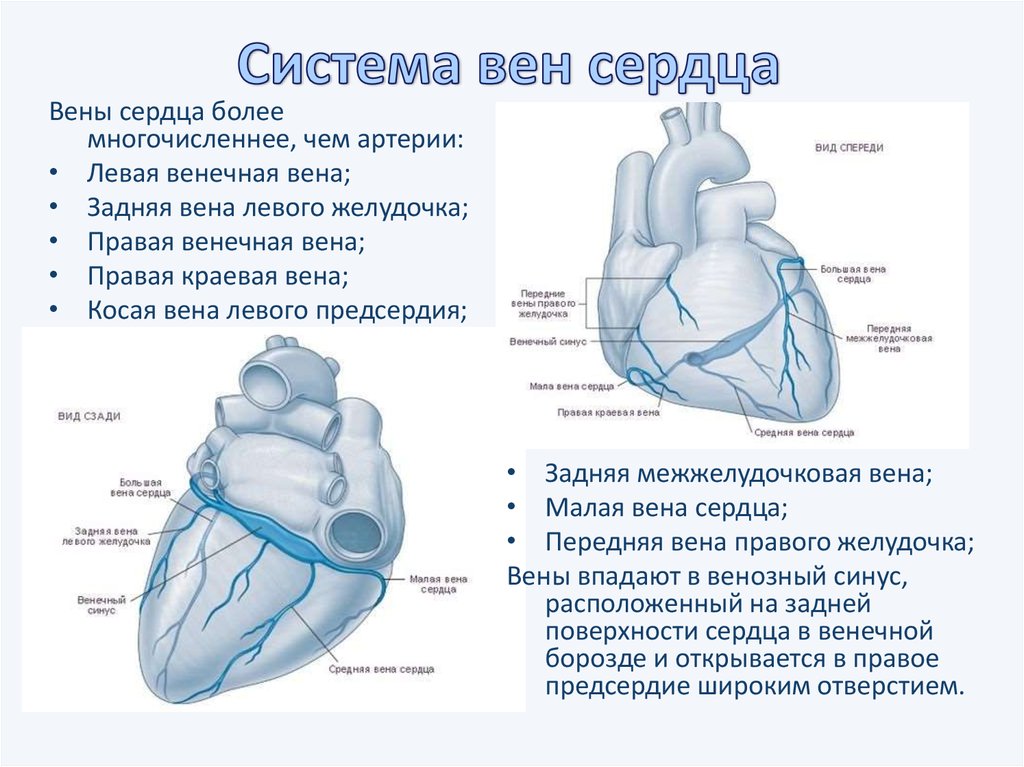

Анатомия коронарных артерий: КТ-изображения